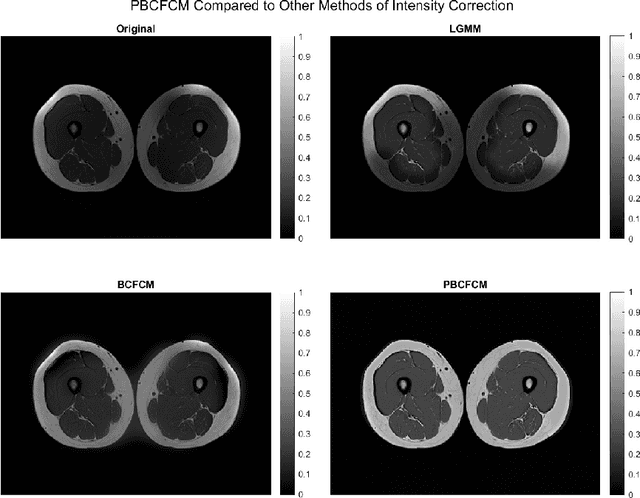

Abstract:Image segmentation is a complex mathematical problem, especially for images that contain intensity inhomogeneity and tightly packed objects with missing boundaries in between. For instance, Magnetic Resonance (MR) muscle images often contain both of these issues, making muscle segmentation especially difficult. In this paper we propose a novel intensity correction and a semi-automatic active contour based segmentation approach. The approach uses a geometric flow that incorporates a reproducing kernel Hilbert space (RKHS) edge detector and a geodesic distance penalty term from a set of markers and anti-markers. We test the proposed scheme on MR muscle segmentation and compare with some state of the art methods. To help deal with the intensity inhomogeneity in this particular kind of image, a new approach to estimate the bias field using a fat fraction image, called Prior Bias-Corrected Fuzzy C-means (PBCFCM), is introduced. Numerical experiments show that the proposed scheme leads to significantly better results than compared ones. The average dice values of the proposed method are 92.5%, 85.3%, 85.3% for quadriceps, hamstrings and other muscle groups while other approaches are at least 10% worse.